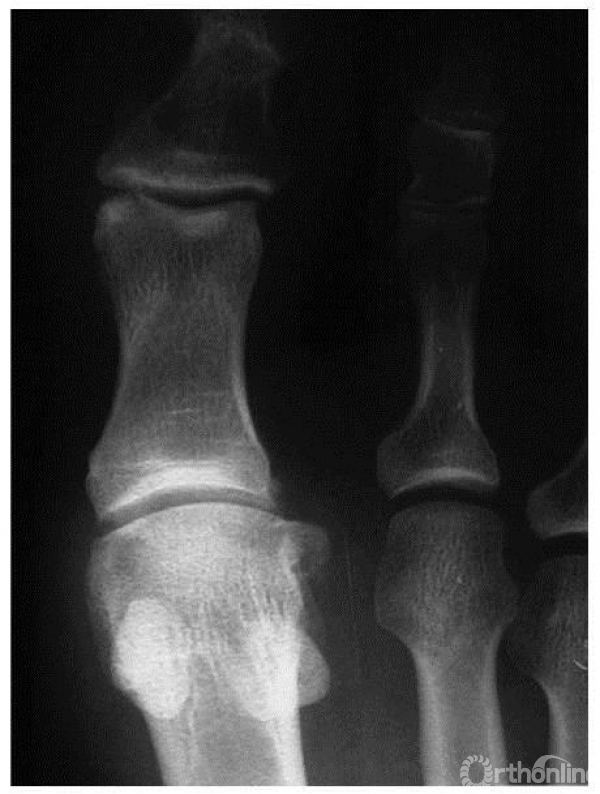

2期:正位X线上,关节外侧缘大量骨赘形成,跖骨头轻度扁平,关节间隙轻度狭窄,伴有骨硬化

2期:侧位X线上,关节间隙变窄,但累及小于1/4的关节间隙(主要累及背侧关节间隙),背侧骨赘较为明显